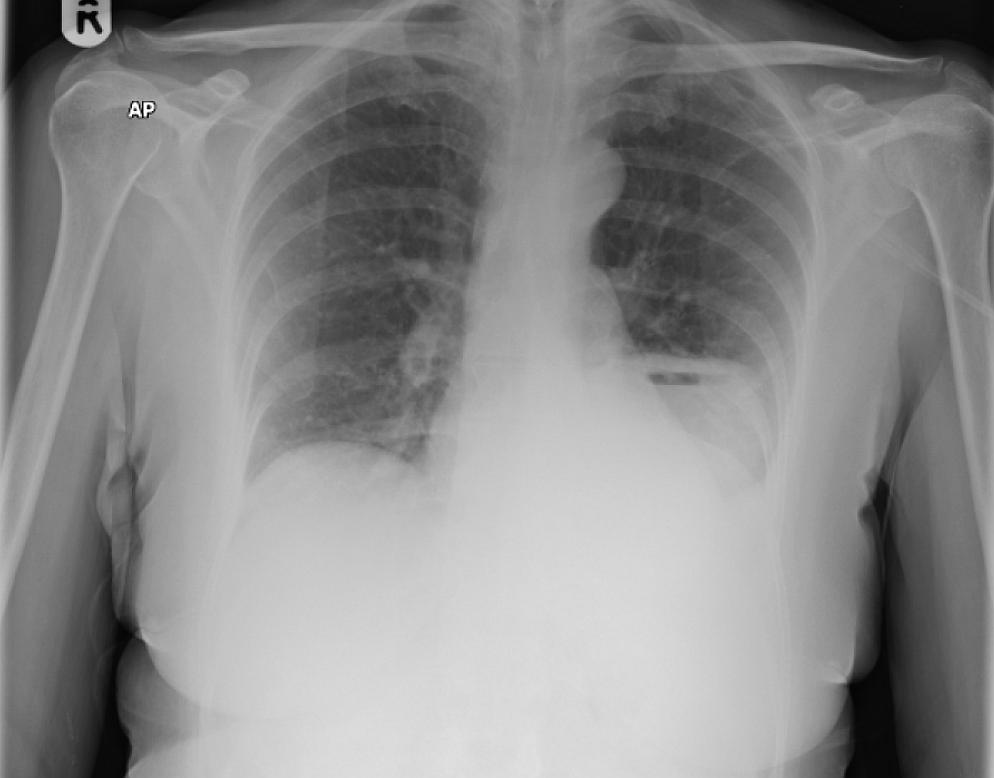

A 62-year-old female patient was admitted with a 4 week history of general malaise, left sided back pain, increasing dyspnoea and cough productive of purulent sputum.

On examination she was pyrexic (38.4), tachycardic, tachypnoeic and hypoxic. Chest was dull to percuss over the left base with bronchial breathing also noted.

What could be the diagnosis ?